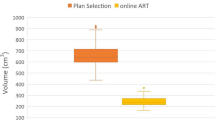

The adaptive treatment for LCRT significantly reduced small bowel V15Gy, V40Gy, V45Gy and V95%, the average volume reduction being approximately 8 cm3. V15Gy and V95% for SCRT were not significantly different (Table 2, Fig. 4).

Boxplot showing difference in volume in cm3 for the small bowel for the different DVH parameters tested for long- and short-course radiation therapy. Negative volume favors the plan-selection strategy. The boxplot shows the interquartile range. Whiskers indicate the 5th and 95th percentiles. Outliers with values between 1.5 and 3.0 IQR (open circle) and extremes > 3.0 IQR (asterisk) are marked

For both treatment schemes, the adaptive treatment significantly reduced all dose volume parameters in the bladder. The difference for V15Gy is very small but the average percentage reduction is approximately 7% (Table 2, Fig. 5).

Boxplot showing difference in volume in percentage for bladder for the different DVH parameters tested for long and short-course radiation therapy. Negative volume favors the plan-selection strategy. The boxplot shows the interquartile range (IQR). Whiskers indicate the 5th and 95th percentiles. Outliers with values between 1.5 and 3.0 IQR (open circle) and extremes > 3.0 IQR (asterisk) are marked